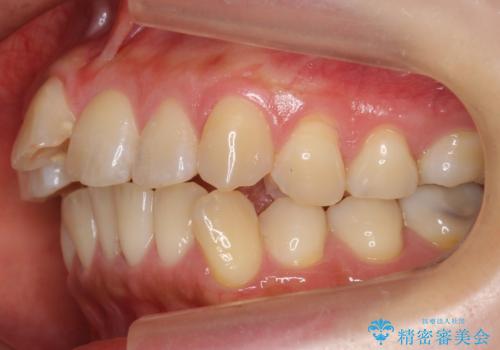

- 前歯の突出を主訴に来院。

上の奥歯を後ろに下げて治療をしました。

矯正用のミニスクリューを使用しています。